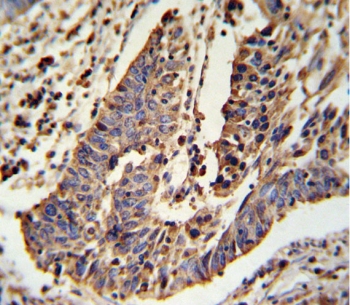

IHC testing of FFPE human lung carcinoma tissue with SCNN1A antibody. HIER: steam section in pH6 citrate buffer for 20 min and allow to cool prior to staining.